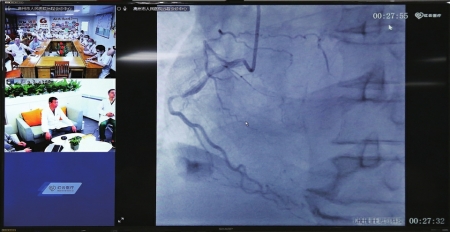

19日上午,来自北京、广州的业界专家汇集高州,分享前沿技术及救治经验。期间,国家心血管疾病临床医学研究中心(首都医科大学附属北京安贞医院)曹向戎主任医师前往高州市人民医院心脏手术室,与高州市人民医院副院长曹勇联手为一名六旬老人手术。老人来自湛江市,心脏三根主干血管堵塞,生命垂危,在北京高州专家强强联手成功进行了心脏搭桥手术后,心脏重焕生机。

目前,心脑血管病、肿瘤性疾病是威胁我国居民健康的最主要“元凶”,在临床有效治疗上还存在不少空白领域。为突破县域心血管病防治的困境,进一步增强“大病不出县”的能力保障,国家心血管疾病临床医学研究中心(首都医科大学附属北京安贞医院)和高州共建合作中心,将在临床研究与成果转化领域进行战略合作,涵盖临床研究、学科建设、双向转诊、人才培养、远程医疗等方面。

心血管病“国家队”资源下沉县域,除了进一步推进国家级优质医疗资源共享,更促进高州心脏病治疗技术水平与国内甚至国际顶尖水平接轨并行。

线上线下把省部级的优质资源带到基层